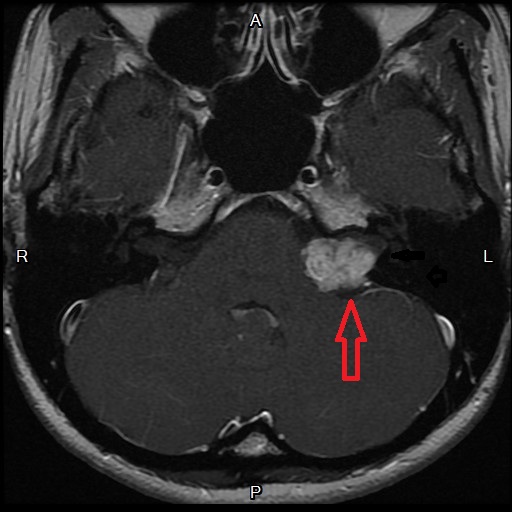

中年女性主訴左耳突發性聽障至本部就診,因左耳聽力完全喪失(圖一)則無聽性腦幹檢查之必要(一定無反應),直接排程核磁共振檢查可見左耳聽神經瘤(圖二)。聽覺反射閾值測驗(圖三)可見:Right Ipsi意謂同側耳右耳給音,右耳聽覺反射正常,可見波峰起伏);Right Contral意謂對側耳左耳給音,右耳聽覺反射消失,不見波峰起伏);Left Ipsi意謂同側耳左耳給音,左耳聽覺反射消失,不見波峰起伏);Left Contra意謂對側耳右耳給音,左耳聽覺反射正常,處可見波峰起伏)。

圖二:左耳聽神經瘤(紅箭頭)。